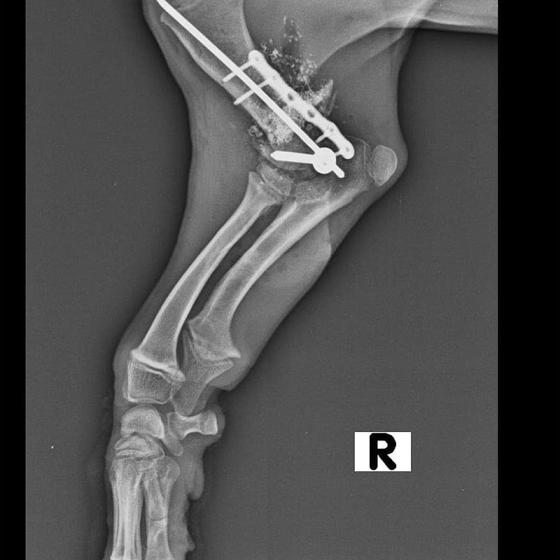

Pluto dnes absolvoval druhú operáciu. Vyberala sa platnička a veľká skrutka, ktorá sa nahradila menším pinom. Koncom mesiaca ho čaká ďalšia a dúfame, že už posledná operácia. Také malinké šteniatko a už toľko bolesti musí prežívať :( Má sa dobre, rastie do krásy a už sa pomaly može naplno šantiť so svojim kamošom v dočasnej opatere. :) Veľmi pekne prosíme, pomôžte nám s úhradou faktúr. Faktúry nájdete priebežne v galérii a na konci článku aj zoznam darcov s prijatou aj chýbajúcou sumou. Po poslednej operácii čakajú Pluta ešte mesiace rehabilitácie, aby sa nožička úplne rozhýbala a mohol ju používať naplno :)

Odoberal sa od drogovo závislých asociálov, ktorý boli vysťahovaný z domu. Ihly, striekačky, ľudské výkaly, rôzne neidentifikovateľné zvratky, špinavé oblečenie, použité kondómy - to všetko nahádzané na jednu kopu v obývačke, kde Pluto so svojou maminkou Miou žili. :( Nevieme ako sa to stalo, kto mu ublížil, ale Pluto má prestrelenú prednú nohu! Viete si predstaviť toho psychicky narušeného človeka, ktorý strieľa na malé bezbranné šteniatko? V dôsledku strelnej rany má doslova rozdrvenú lakťovú kosť. Mali sme veľké obavy, že o nožičku príde, ale MVDr. Vatolík s teamom veterinárnej kliniky Sibra centrum opäť urobil zázrak a malému nožičku napravil a prognóza je viac než dobrá. Čaká ho ešte dlhá cesta k zotaveniu, ale je to odvážny a statočný bojovník. Nechceme si ani len predstaviť čím všetkým si tie zvieratká muesli prejsť, a kto vie koľko ich pôvodne bolo.. Nikto nevie ako a kde skončili Plutovi súrodenci...